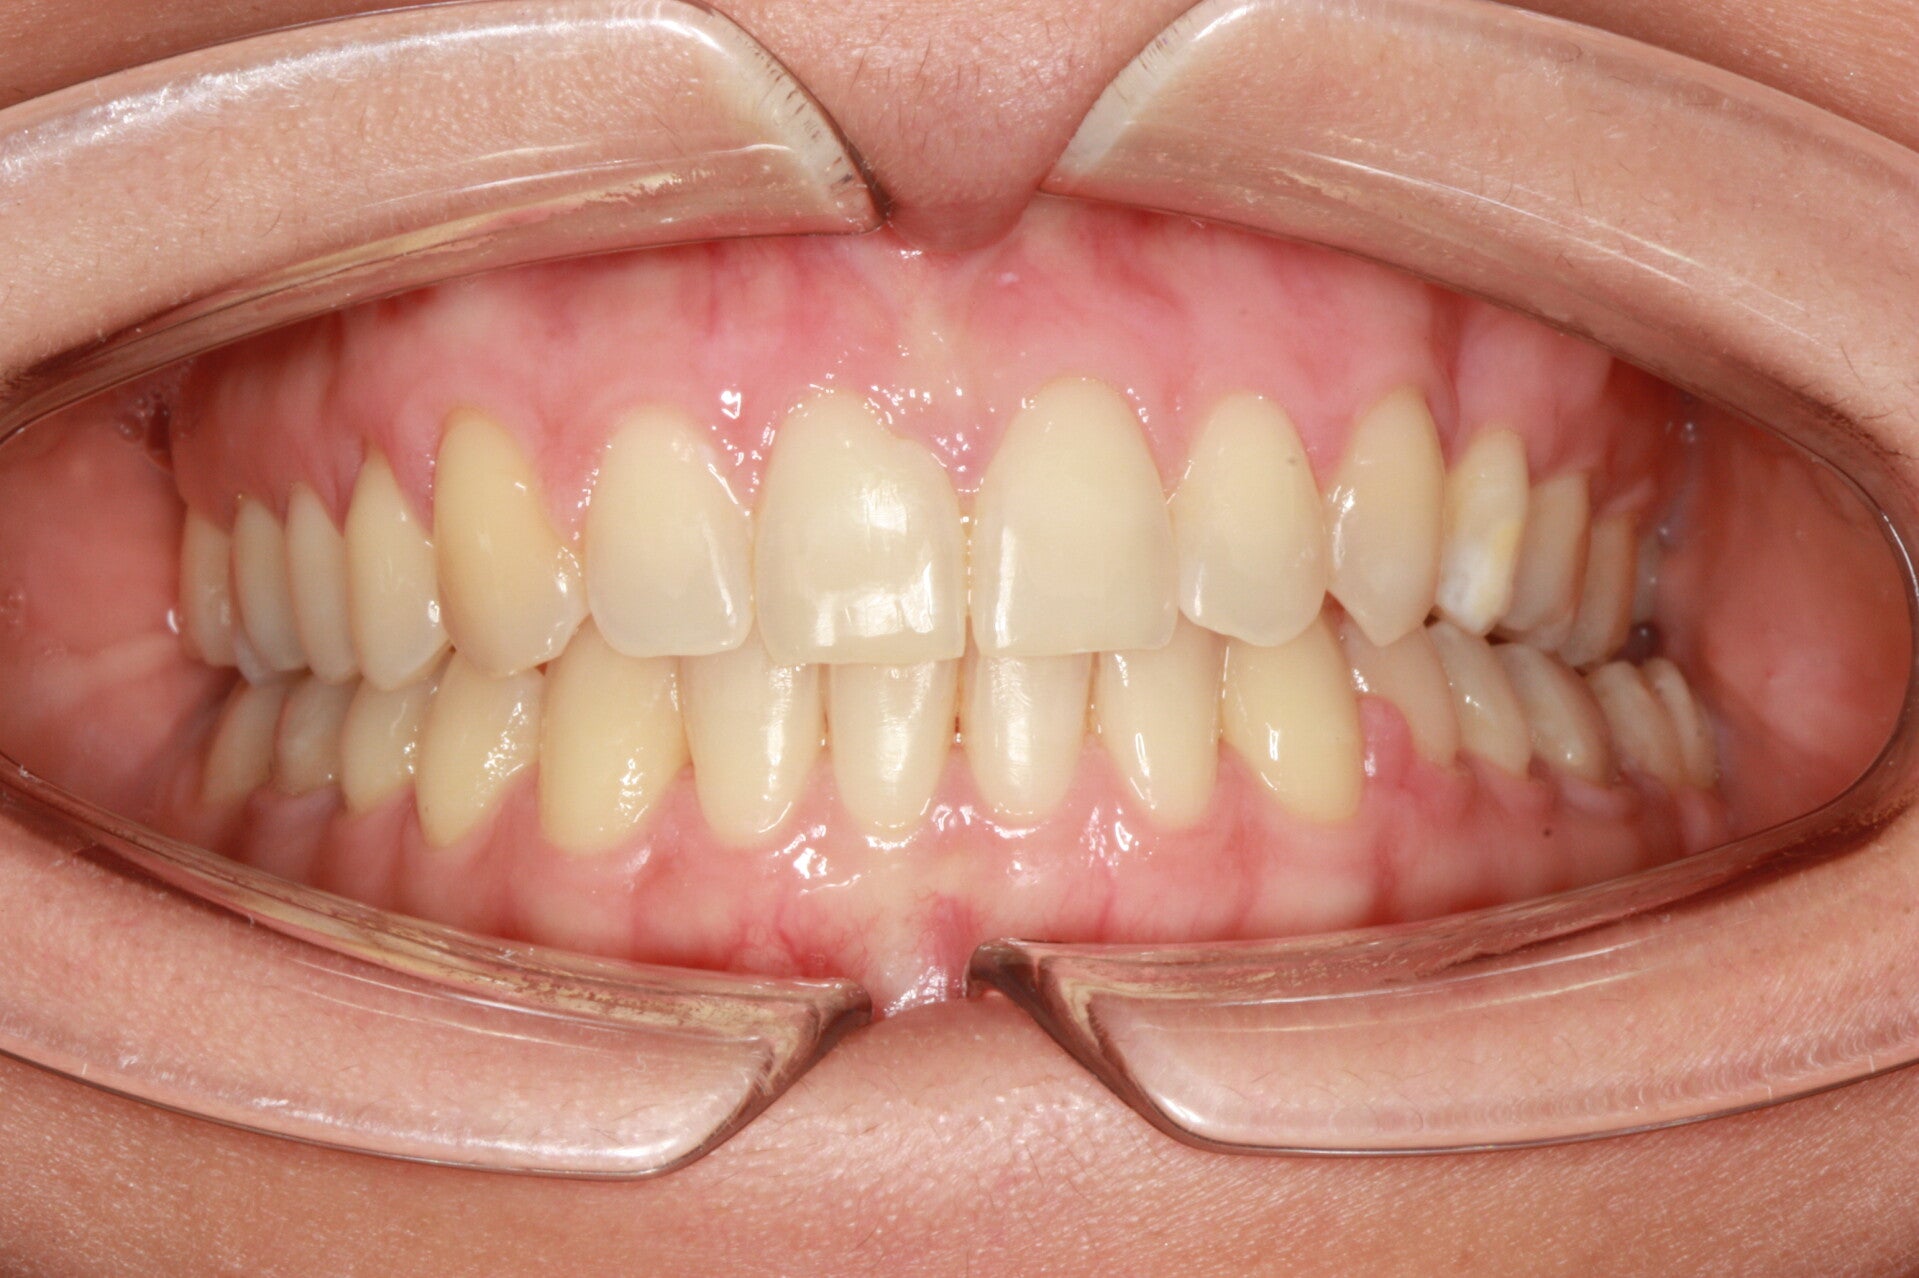

FOTO FINALI DOPO 24 MESI CIRCA DI TERAPA ORTODONTICA FISSA

PRIMA CLASSE CON AFFOLLAMENTO GRAVE SUPERIORE A SINISTRA CON PERDITA PRECOCE DEL SECONDO MOLARE INFERIORE SINISTRO

Abbiamo appena portato a termine questo caso che presentava in arcata superiore il primo premolare di sinistra completamente fuori arcata sovrapposto al secondo premolare ed il canino ruotato.

in arcata inferiore invece abbiamo estratto il secondo molare di sinistra perso per carie deostruente e mesializzato il terzo molare in modo da chiudere lo spazio e non ricorrere all'inserimento di protesi implantare.